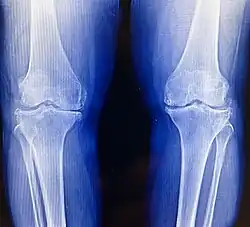

Imaging tests like X-rays are commonly utilized to diagnose and monitor arthritis.[61] Other imaging tests for rheumatoid arthritis that may be considered include computed tomography (CT) scanning, positron emission tomography (PET) scanning, bone scanning, and dual-energy X-ray absorptiometry (DEXA).[61]

Osteoarthritis (OA) is the most common form of arthritis.[62] It affects humans and other animals, notably dogs, but also occurs in cats and horses. It can affect both the larger (i.e. knee, hip, shoulder, etc.) and the smaller joints (i.e. fingers, toes, foot, etc.) of the body. The disease is caused by daily wear and tear of the joint. This process can progress more rapidly as a result of injury to the joint. Osteoarthritis is caused by the break down of the smooth surface between two bones, known as cartilage, which can eventually lead to the two opposing bones coming in direct contact and eroding one another. OA symptoms typically begin with minor pain during physical activity, but can eventually progress to be present at rest. The pain can be debilitating and prevent one from doing activities that they would normally do as part of their daily routine. OA typically affects the weight-bearing joints, such as the back, knee and hip due to the mechanical nature of this disease process. Unlike rheumatoid arthritis, osteoarthritis is most commonly a disease of the elderly. The strongest predictor of osteoarthritis is increased age, likely due to the declining ability of chondrocytes to maintain the structural integrity of cartilage.[63] More than 30 percent of women have some degree of osteoarthritis by age 65. One of the primary tools for diagnosing OA are X-rays of the joint. Findings on X-ray that are consistent with OA include those with joint space narrowing (due to cartilage breakdown), bone spurs, sclerosis, and bone cysts.[64]